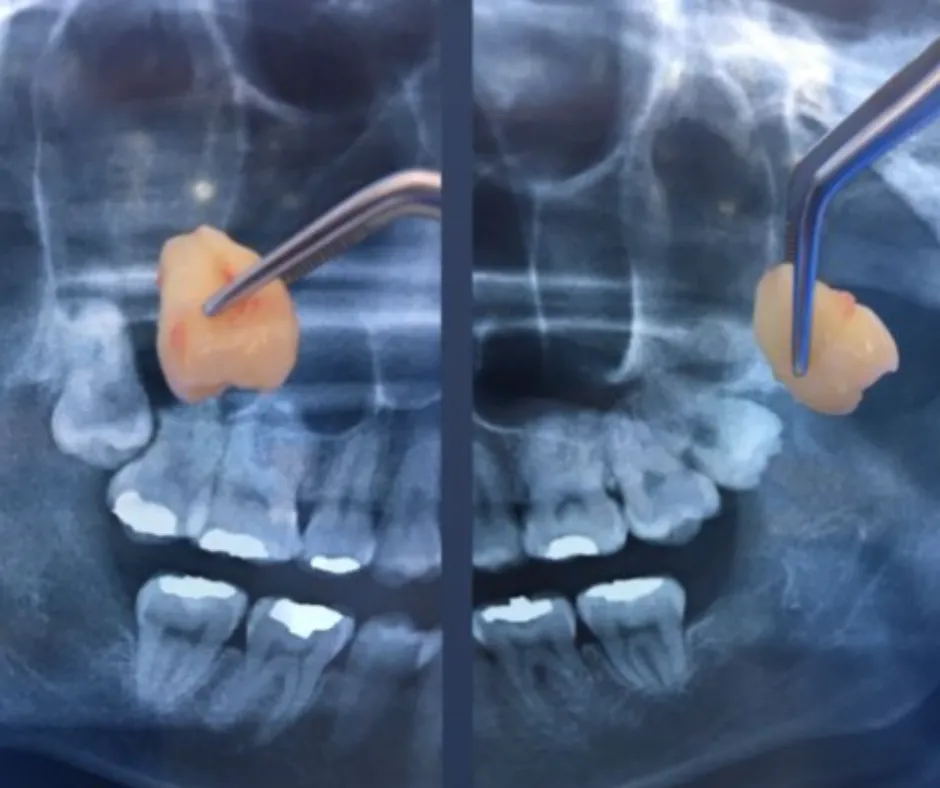

Vemos exactamente dónde están raíces, nervios y posición real.

Radiografía panorámica.

Explicación clara de tu caso (con la imagen en pantalla).

Plan de tratamiento para tus muelas del juicio.